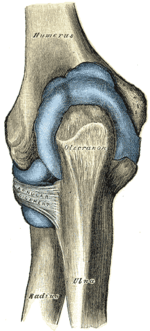

Left: anterior and ulnar collateral ligaments

Right: posterior and radial collateral ligaments

The elbow, like other joints, has ligaments on either side. These are triangular bands which blend with the joint capsule. They are positioned so that they always lie across the transverse joint axis and are, therefore, always relatively tense and impose strict limitations on abduction, adduction, and axial rotation at the elbow.[7]

The ulnar collateral ligament has its apex on the medial epicondyle. Its anterior band stretches from the anterior side of the medial epicondyle to the medial edge of the coronoid process, while the posterior band stretches from posterior side of the medial epicondyle to the medial side of the olecranon. These two bands are separated by a thinner intermediate part and their distal attachments are united by a transverse band below which the synovial membrane protrudes during joint movements. The anterior band is closely associated with the tendon of the superficial flexor muscles of the forearm, even being the origin of flexor digitorum superficialis. The ulnar nerve crosses the intermediate part as it enters the forearm.[7]

The radial collateral ligament is attached to the lateral epicondyle below the common extensor tendon. Less distinct than the ulnar collateral ligament, this ligament blends with the annular ligament of the radius and its margins are attached near the radial notch of the ulna.[7]